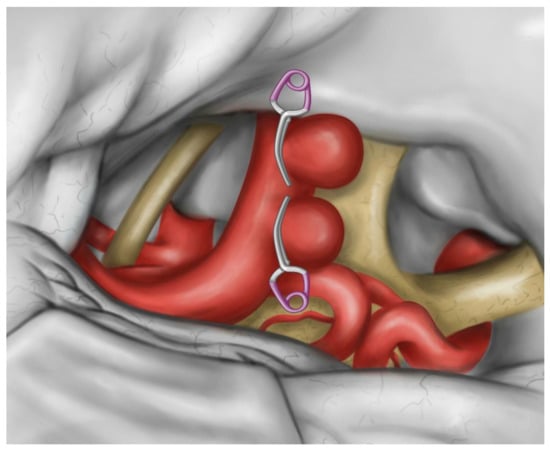

Microsurgical Clipping of Carotid-Ophthalmic Tandem Aneurysms: Case Report and Surgical Nuances

Costa, M.; Baldoncini, M.; Tataryn, Z.L.; Demichelis, M.E.; Conde, A.; Purves, C.; Giotta Lucifero, A.; Hernesniemi, J.; Luzzi, S. Microsurgical Clipping of Carotid-Ophthalmic Tandem Aneurysms: Case Report and Surgical Nuances. Medicina 2021, 57, 731. https://doi.org/10.3390/medicina57070731